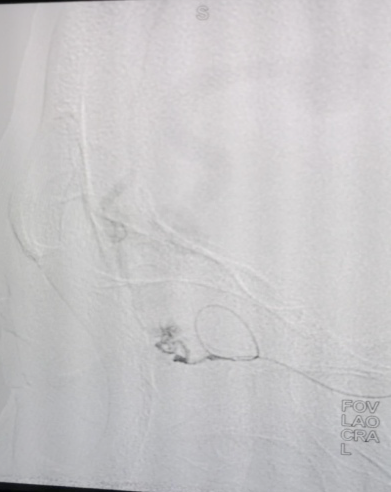

▲三维重建

▲术中情况

此类疾病常规开刀手术无法完成,必须通过神经介入血管内治疗,和家属沟通后,在外请专家指导下,在介入科、手术麻醉科的大力协助下,神经外科二病区神经介入脑血管病诊疗团队顺利为患者实施手术,手术过程顺利,术后造影提示眼动脉血流缓慢但视网膜中央动脉血流通畅,视网膜染色正常,视力正常,为防止眼动脉血栓闭塞视网膜中央动脉,给予低分子肝素钙皮下注射。术后患者症状即刻消失,现正继续后续治疗。